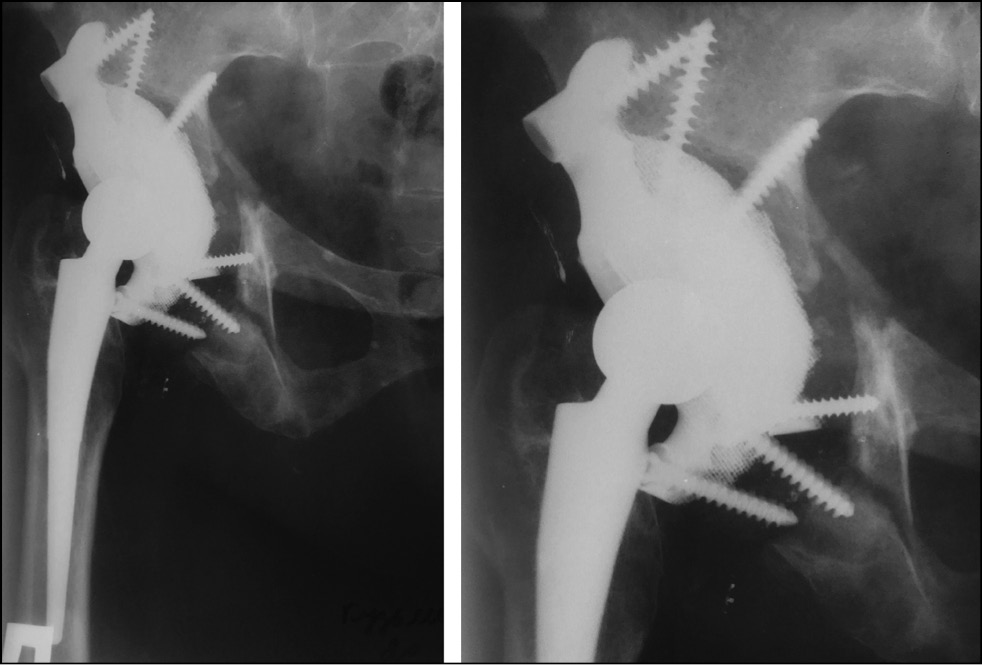

Six months after surgery, no negative dynamics on control radiographs were observed. The HHS, WOMAC, and VAS scores were 82, 15, and 30 (mm) points, respectively. Despite a slight increase in the severity of pain syndrome according to the VAS score, the patient noted improvement in the bearing capacity and functional results of the operated limb. No significant changes in the evaluation scales were noted at the subsequent follow-up examinations (1 year after surgery and once a year thereafter). At the time of writing, >4 years have elapsed since the operation. Data obtained four years after surgery did not show negative dynamics on control radiographs (Fig. 8). The pain syndrome slightly increased and corresponds to 32 (mm) points on the VAS scale. On the HHS scale, the hip joint function corresponded to 74 points, and social adaptation according to the WOMAC scale corresponded to 35 points. The patient is under dynamic observation.

Fig. 8. Postoperative control X-ray 4 years after the operation.